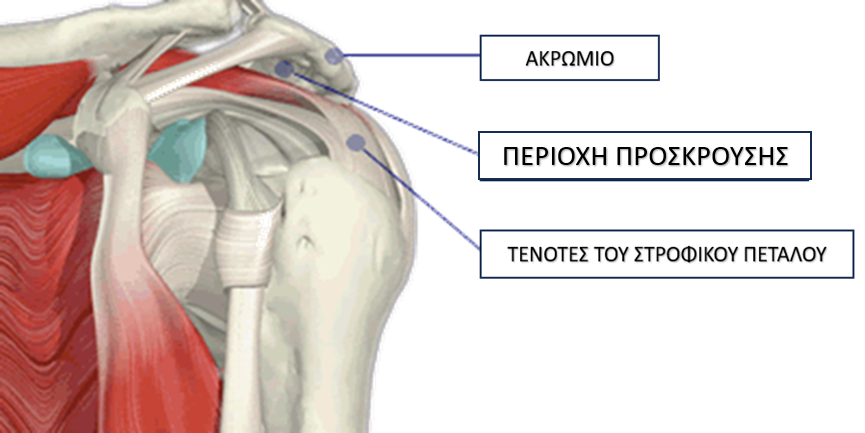

Σύνδρομο Υπακρωμιακής Προστριβής του Ώμου

Τι Είναι;

Το σύνδρομο υπακρωμιακής προστριβής ή σύνδρομο πρόσκρουσης προκαλείται από την μείωση της απόστασης (<7 χιλ), ανάμεσα στην κεφαλή του βραχιονίου οστού και του ακρωμίου (προεξοχή της ωμοπλάτης), με αποτέλεσμα τη φλεγμονή του υπακρωμιακού ορογόνου θυλάκου (bursa) και τον μηχανικό ερεθισμό των τενόντων του στροφικού πετάλου οι οποίοι διέρχονται από αυτό το διάστημα.